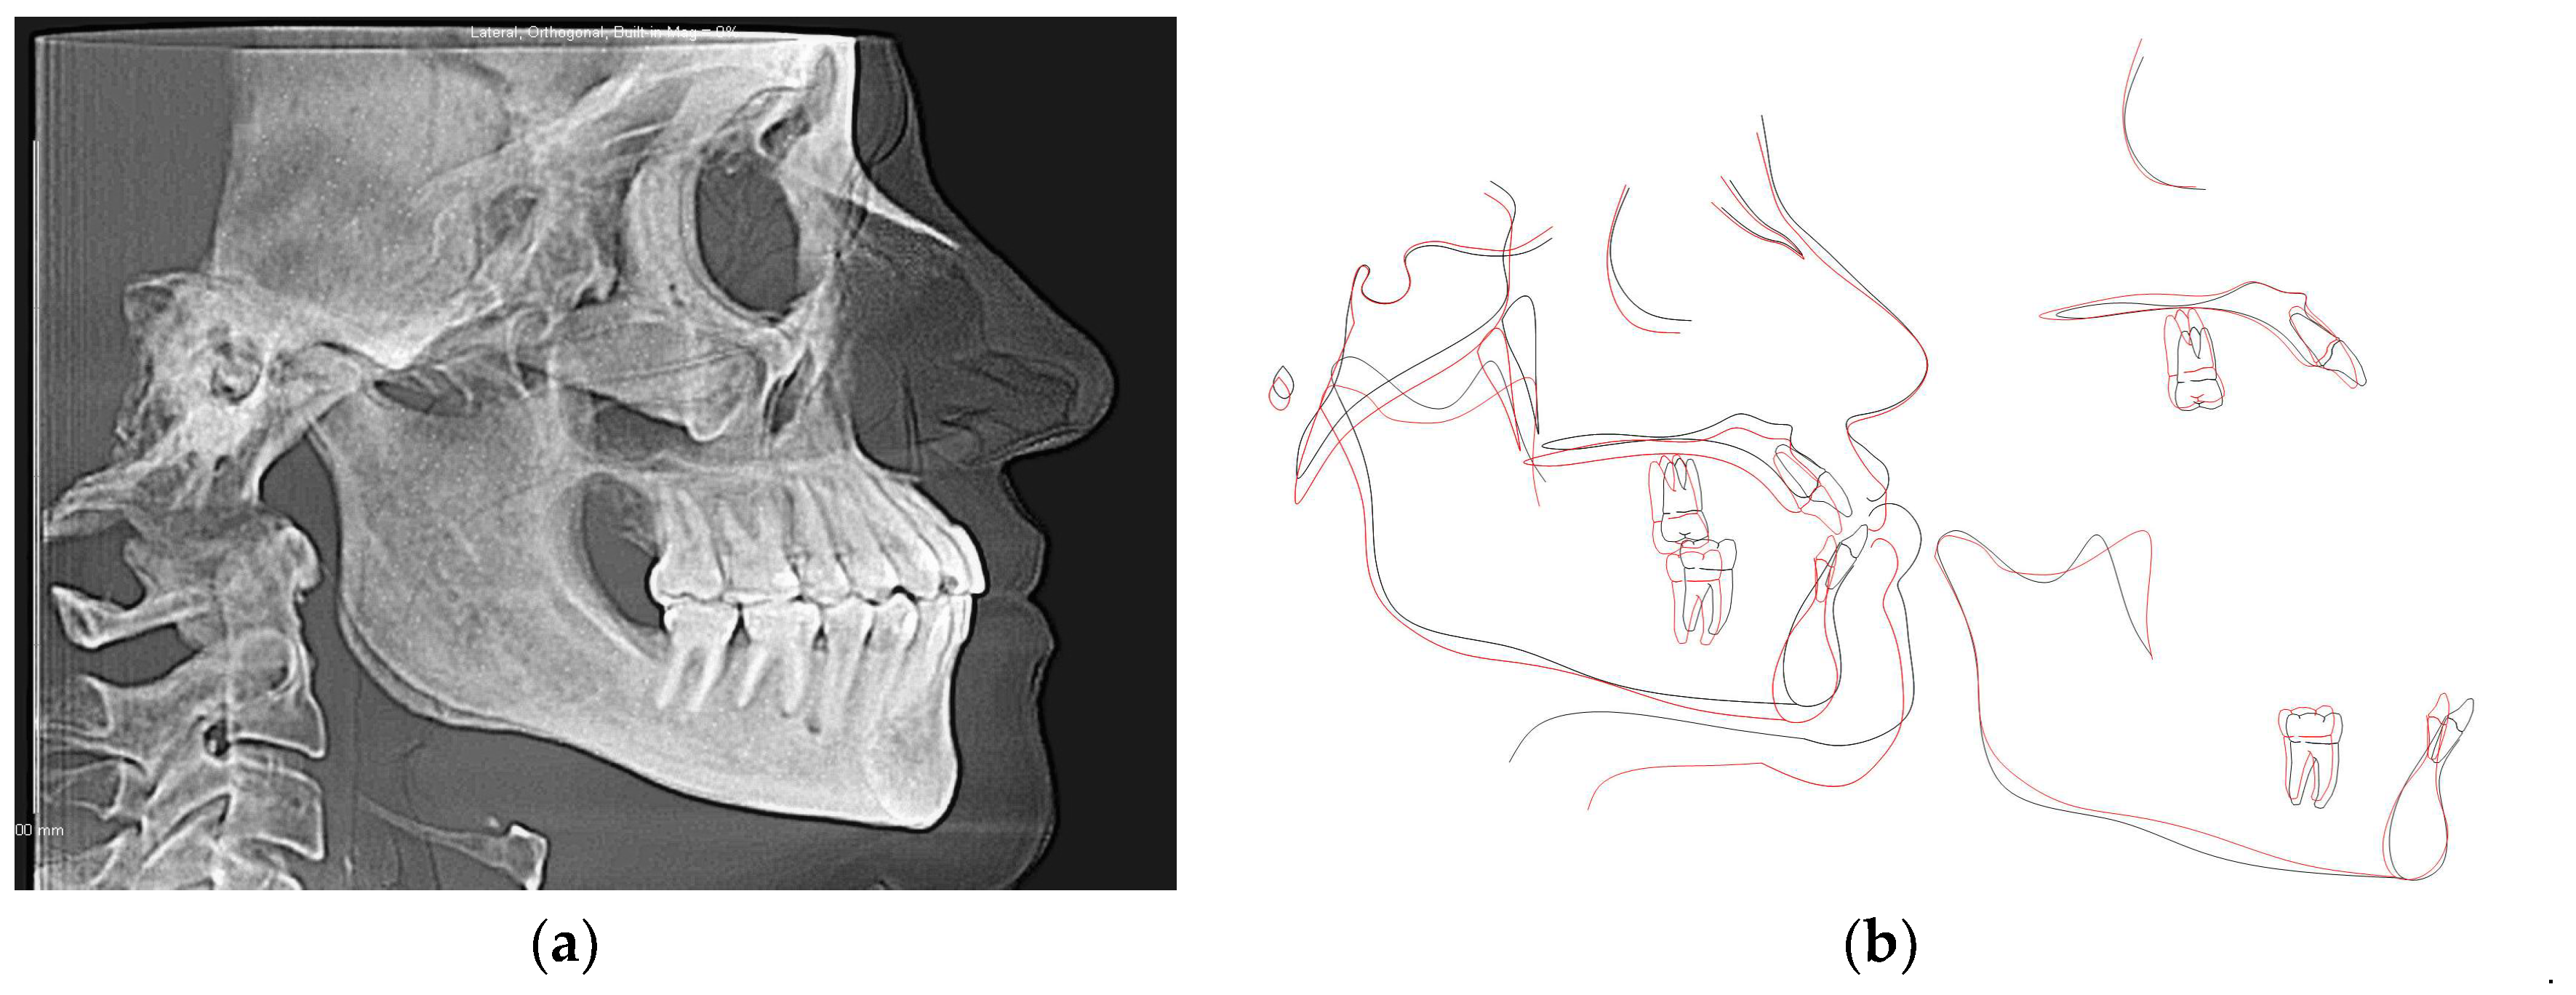

3.2. CBCT-Driven Radiographs

3.2.1. Cephalometric Radiographs and Analysis

| Measurement | Initial | Final | Norm |

|---|---|---|---|

| SNA (°) | 86.2 | 86.3 | 82 |

| SNB (°) | 86.7 | 86 | 80.9 |

| SN - MP (°) | 28.9 | 29.8 | 32.9 |

| FMA (MP-FH) (°) | 20.8 | 18.9 | 23.9 |

| ANB (°) | −0.5 | 0.3 | 1.6 |

| U1 - NA (mm) | 7.5 | 4.8 | 4.3 |

| U1 - SN (°) | 119 | 109.9 | 102.8 |

| L1 - NB (mm) | 9.4 | 3.7 | 4 |

| L1 - MP (°) | 106.3 | 87.4 | 95 |

| Lower Lip to E-Plane (mm) | 0.5 | −2.8 | −2 |

| Upper Lip to E-Plane (mm) | −6.8 | −6 | −6 |